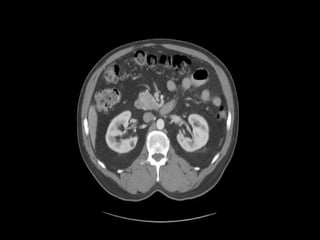

Abdominal CT Scan Crossing the barrier in bedside interpretation 2. Can a Clinician interpret CT scan like a Radiologist. CONTRAST ENHANCED CT 2 ml 4mlsec Total 150 ml Large bore iv catheter18-20 gauge Time of the bolus in relation to the scan varies.

Computed tomography is a computerized x-ray based imaging procedure that generates cross-sectional images or slices of the body. Computed tomography is a computerized x-ray based imaging procedure that generates cross-sectional images or slices of the body. Your request will be confirmed within one business day but usually within a few hours. A combination of computed tomography CT scan and retrograde urethrogram is routinely employed to simulate treatment portals prior to radiation therapy for prostate cancer. Medshare supports CAT Scan computed tomography MRI Magnetic resonance imaging X-RAY CBCT Cone beam computed tomography CTA Computed tomography angiography and many more. The benefit of a complete abdominal scan is that alternative diagnoses are made in up to 15 percent of patients 8. Find Yourself First. Rotating multiarray xray generators and detectors with slipring contacts allowing continuous spiral or helical data acquisition Radiation Dose Variable. What is a Chest CT.

Based on a systematic review of patients with suspected appendicitis the sensitivity and specificity of a pelvic and abdominal CT scan are 94 percent and 95 percent respectively 7. CONTRAST ENHANCED CT 2 ml 4mlsec Total 150 ml Large bore iv catheter18-20 gauge Time of the bolus in relation to the scan varies. A combination of computed tomography CT scan and retrograde urethrogram is routinely employed to simulate treatment portals prior to radiation therapy for prostate cancer. View the sourcing details of the buying request titled CT Scan including both product specification and requirements for supplier. Chest CT for Non-Radiologists A Practical Guide. The benefit of a complete abdominal scan is that alternative diagnoses are made in up to 15 percent of patients 8. CT Made ECasy - Free download as Powerpoint Presentation ppt PDF File pdf Text File txt or view presentation slides online.